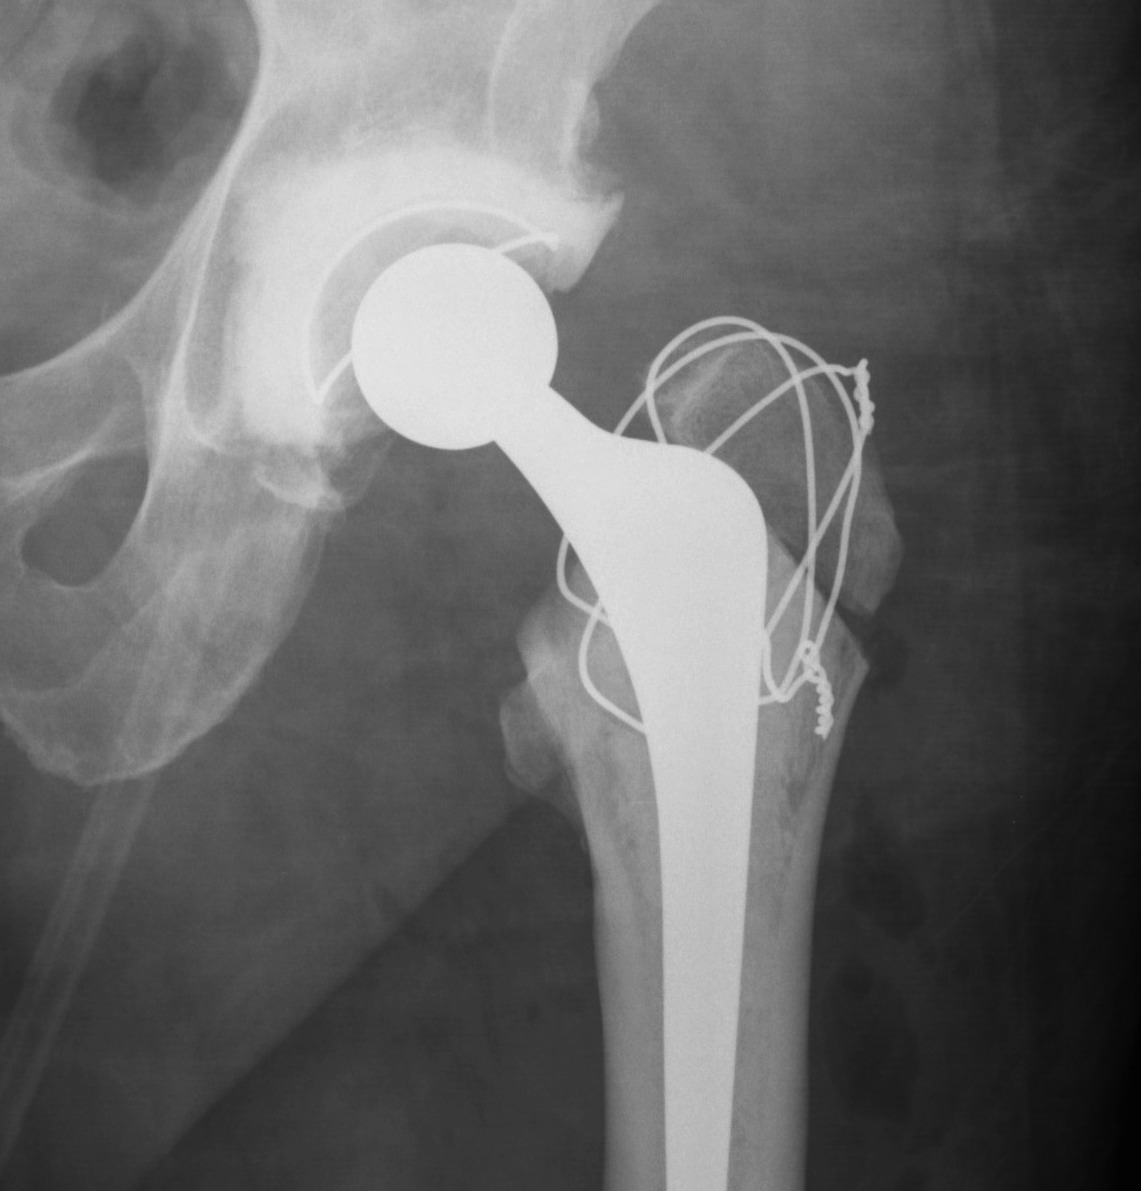

Trochanteric Osteotomy

Types

1. Standard trochanteric osteotomy

2. Sliding trochanteric osteotomy

3. Extended trochanteric osteotomy